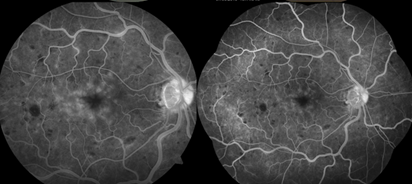

A 35-year-old, male, Caucasian patient presented to our clinic with complain of blurred vision in his right eye. Unilateral blurred and low vision has persisted for 6-month and the patient had been underwent an intravitrealinjection in the clinic. The patient was underwent a detailed ophthalmological examination. The best corrected visual acuity (BCVA) was found as 20/32 in the right eye and 20/20 in the left eye with Snellen chart. Intraocular pressure was bilateral 15mmHg with Goldmann applanation tonometer. In biomicroscopic examinations was completely normal for two eyes. After dilation, retinal arterial narrowing, arteriovenous nipping, retinal hemorrhages, roth spots, and loss of foveal light reflex were seen in the right fundus while the left fundus was completely normal (Figure 1). In optical coherence tomography (OCT), diffuse macular thickening in the right eye and normal macular configuration in the left eye were seen Figure 2. Fundus fluorescein angiography (FFA) was performed and delay in arterial filling, capillary drop-out, and foveal late-phase leakage were present in the right eye although left eye was normal (Figure 3). We looked for an anterior and posterior segment neovascularization using 3-mirror lens and we planned to closely follow-up for the patient because of there was no any neovascularization in clinical examination and suspicious leakage in previous FFA.

Figure 3 Fundus fluorescein angiography images of the patient.